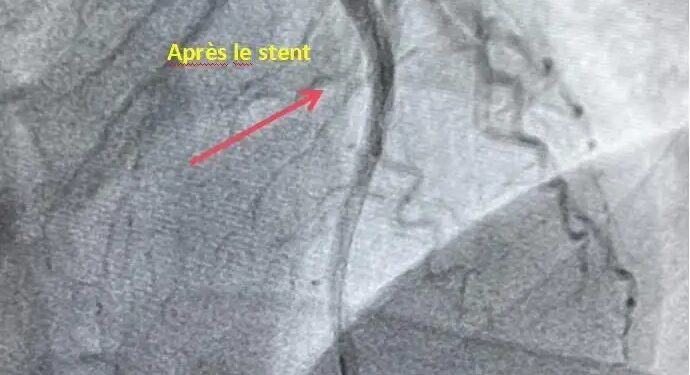

D’après les responsables médicaux de l’établissement, l’examen a mis en évidence une occlusion totale de la portion médiane de l’artère interventriculaire antérieure branche de l’artère coronaire gauche avec un flux sanguin classé TIMI 0. Une intervention de revascularisation a été immédiatement entreprise, permettant une reperfusion efficace grâce à la pose d’un stent. Le flux coronarien a ainsi été restauré à un niveau TIMI 3.